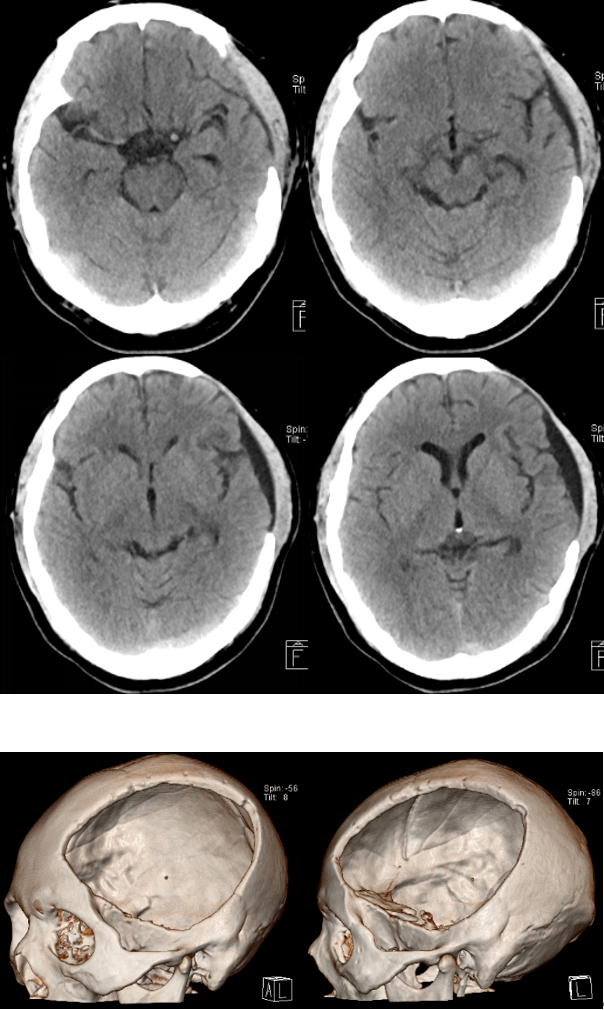

3.专科检查:T:36.6℃、P:96次/分、R:21次/分、BP:147/84mmHg、GCS6(E1V1M4)分,昏迷状态,查体不合作,头颅五官未见畸形,右侧瞳孔直径约3.0mm,对光反射灵敏,左侧瞳孔直径约4.5mm,对光反射消失;颈阻(+),四肢刺痛屈曲,生理反射存在,病理征阴性。

4.头颅CT(2022-10-22):

入院诊断:

1.创伤性蛛网膜下腔出血

2.左侧额颞顶部硬膜下血肿

3.大脑镰下疝

4.右侧颞极蛛网膜囊肿